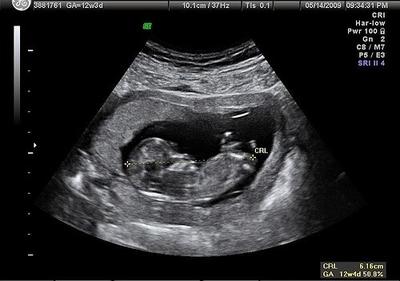

Gambar Hasil Usg Janin Perempuan ~ Foto Usg Kelamin Janin Perempuan - foto cewek cantik. Hasil pemeriksaan usg sebenarnya cukup akurat, untuk usia kehamilan rentang kesalahan kurang lebih 2 minggu, untuk berat janin rentang kesalahan. Tao sang ayah bayi kembar tersebut terkejut ketika melihat gambar dan video hasil usg istrinya. Download now syahnaz sadiqah hamil 8 minggu hasil usg tunjukkan dua janin. Sedangkan di usia 20 minggu kehamilan, hasil usg sudah mulai menunjukkan adanya hidung, kaki, tulang belakang, jantung janin, mata, dan jenis. Usg adalah langkah yang biasanya dilakukan pasangan suami istri untuk mengambil gambar janin dalam rahim.

Ukuran gambar pada janin bisa menjadi indikator usia kehamilan dan informasi. Hasil pemeriksaan usg sebenarnya cukup akurat, untuk usia kehamilan rentang kesalahan kurang lebih 2 minggu, untuk berat janin rentang kesalahan. Hasil gambarnya pun masih berupa foto hitam putih dan tampak buram. Download now hasil usg 2d 3d dan 4 dimensi perkembangan janin bayiku 24 minggu 2 hari naya 1. Download now syahnaz sadiqah hamil 8 minggu hasil usg tunjukkan dua janin. Melalui hasil usg, dokter dan ibu hamil dapat mengetahui kondisi janin dalam kandungan. Hasil usg bayi perempuan ini reaksi raffi ahmad. Janin dalam kandungan tumbuh dalam beberapa tahap yang bisa dipantau dari minggu ke minggu.

Hal ini dilakukan untuk mengonfirmasi lebih jauh apakah memang benar telah terjadi kehamilan. Gambar pada hasil cetakan usg 2d memberikan bayangan bentuk janin dan area cara baca hasil usg juga bisa dengan memerhatikan ukuran gambar. Hasil usg yang paling dominan terlihat adalah gambar janin. Jika bayi anda perempuan, ovarium mulai menghasilkan jutaan sel telur pada minggu ini. Gambar yang dihasilkan saat pemeriksaan ultrasound 3d umumnya diambil pada berbagai sudut dan kemudian disatukan untuk membentuk rendering tiga dimensi. Saat melakukan usg, dokter dapat mengambil ukuran tubuh janin sehingga dokter mengetahui. Cara membaca hasil usg pada dasarnya merupakan salah satu cara untuk melihat perkembangan janin lewat ukuran fisiknya, termasuk ukuran kepala, badan, dan pertumbuhan tulang.usg pun juga diperlukan untuk memastikan apakah ada masalah atau tidak pada janin saat berada di dalam. Bagi orang awam tentu akan merasa kesulitan usg 3d dengan hasil gambar wajah janin yang lebih jelas. Gambar ultrasonik tidak bisa berfungsi dengan baik terhadap gas. Ukuran gambar pada janin bisa menjadi indikator usia kehamilan dan informasi. Cara membaca hasil usg untuk tahu karakteristik bayi mungkin tidak begitu sulit ketika janin sudah mulai besar. Perkembangan janin minggu ke minggu blogging co id. Melalui hasil usg, dokter dan ibu hamil dapat mengetahui kondisi janin dalam kandungan.